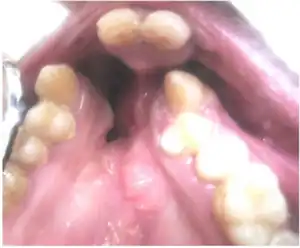

There are three types of lip pits, which are classified according to their location: midline upper, comissural, and lower lip. The most common phenotype is two symmetrical lower lip pits flanking both sides of the midline in the bilateral paramedial sinuses. Lower lip pits may also be bilaterally, unilaterally, or medially asymmetrical. The occurrence of a single lip pit is considered incomplete expression, and it typically occurs on the left side of the lower lip. There are also three different shapes for lip pits, the most common being circular or oval; less common forms include slit-like or transverse. The lip pits extend into the orbicularis oris muscle, ending in blind sacs surrounded by mucous glands. In some cases mucous is excreted when the muscles contract.[4]

Clinical diagnosis based on orofacial clefts and lip pits typically occurs shortly after birth. Certain defects may be difficult to diagnose, particularly a submucous cleft palate. This form of CP may not be detected except through finger palpation, as the mucosa covering the palate is intact, but the muscles underneath have lost their proper attachments. Feeding problems, impaired speech, and hearing loss are symptoms of a submucous cleft palate.[3] Furthermore, approximately 15% of VWS cases with orofacial clefts, in the absence of prominent lip pits, cannot be easily distinguished from non-syndromic forms of orofacial clefting.[7] Therefore, it is very important to closely examine these patients as well as their relatives for lip pits, especially when there is a family history of mixed clefting, in order to make the VWS diagnosis.[4] Dentists may also play an important role in diagnosing cases not detected at birth, as they detect hypodontia commonly associated with VWS. The patients most commonly lack the upper second premolars followed by the lower second premolars and upper lateral incisors. The absence of these teeth might play a role in the constricting of the dental arches.[4][3]